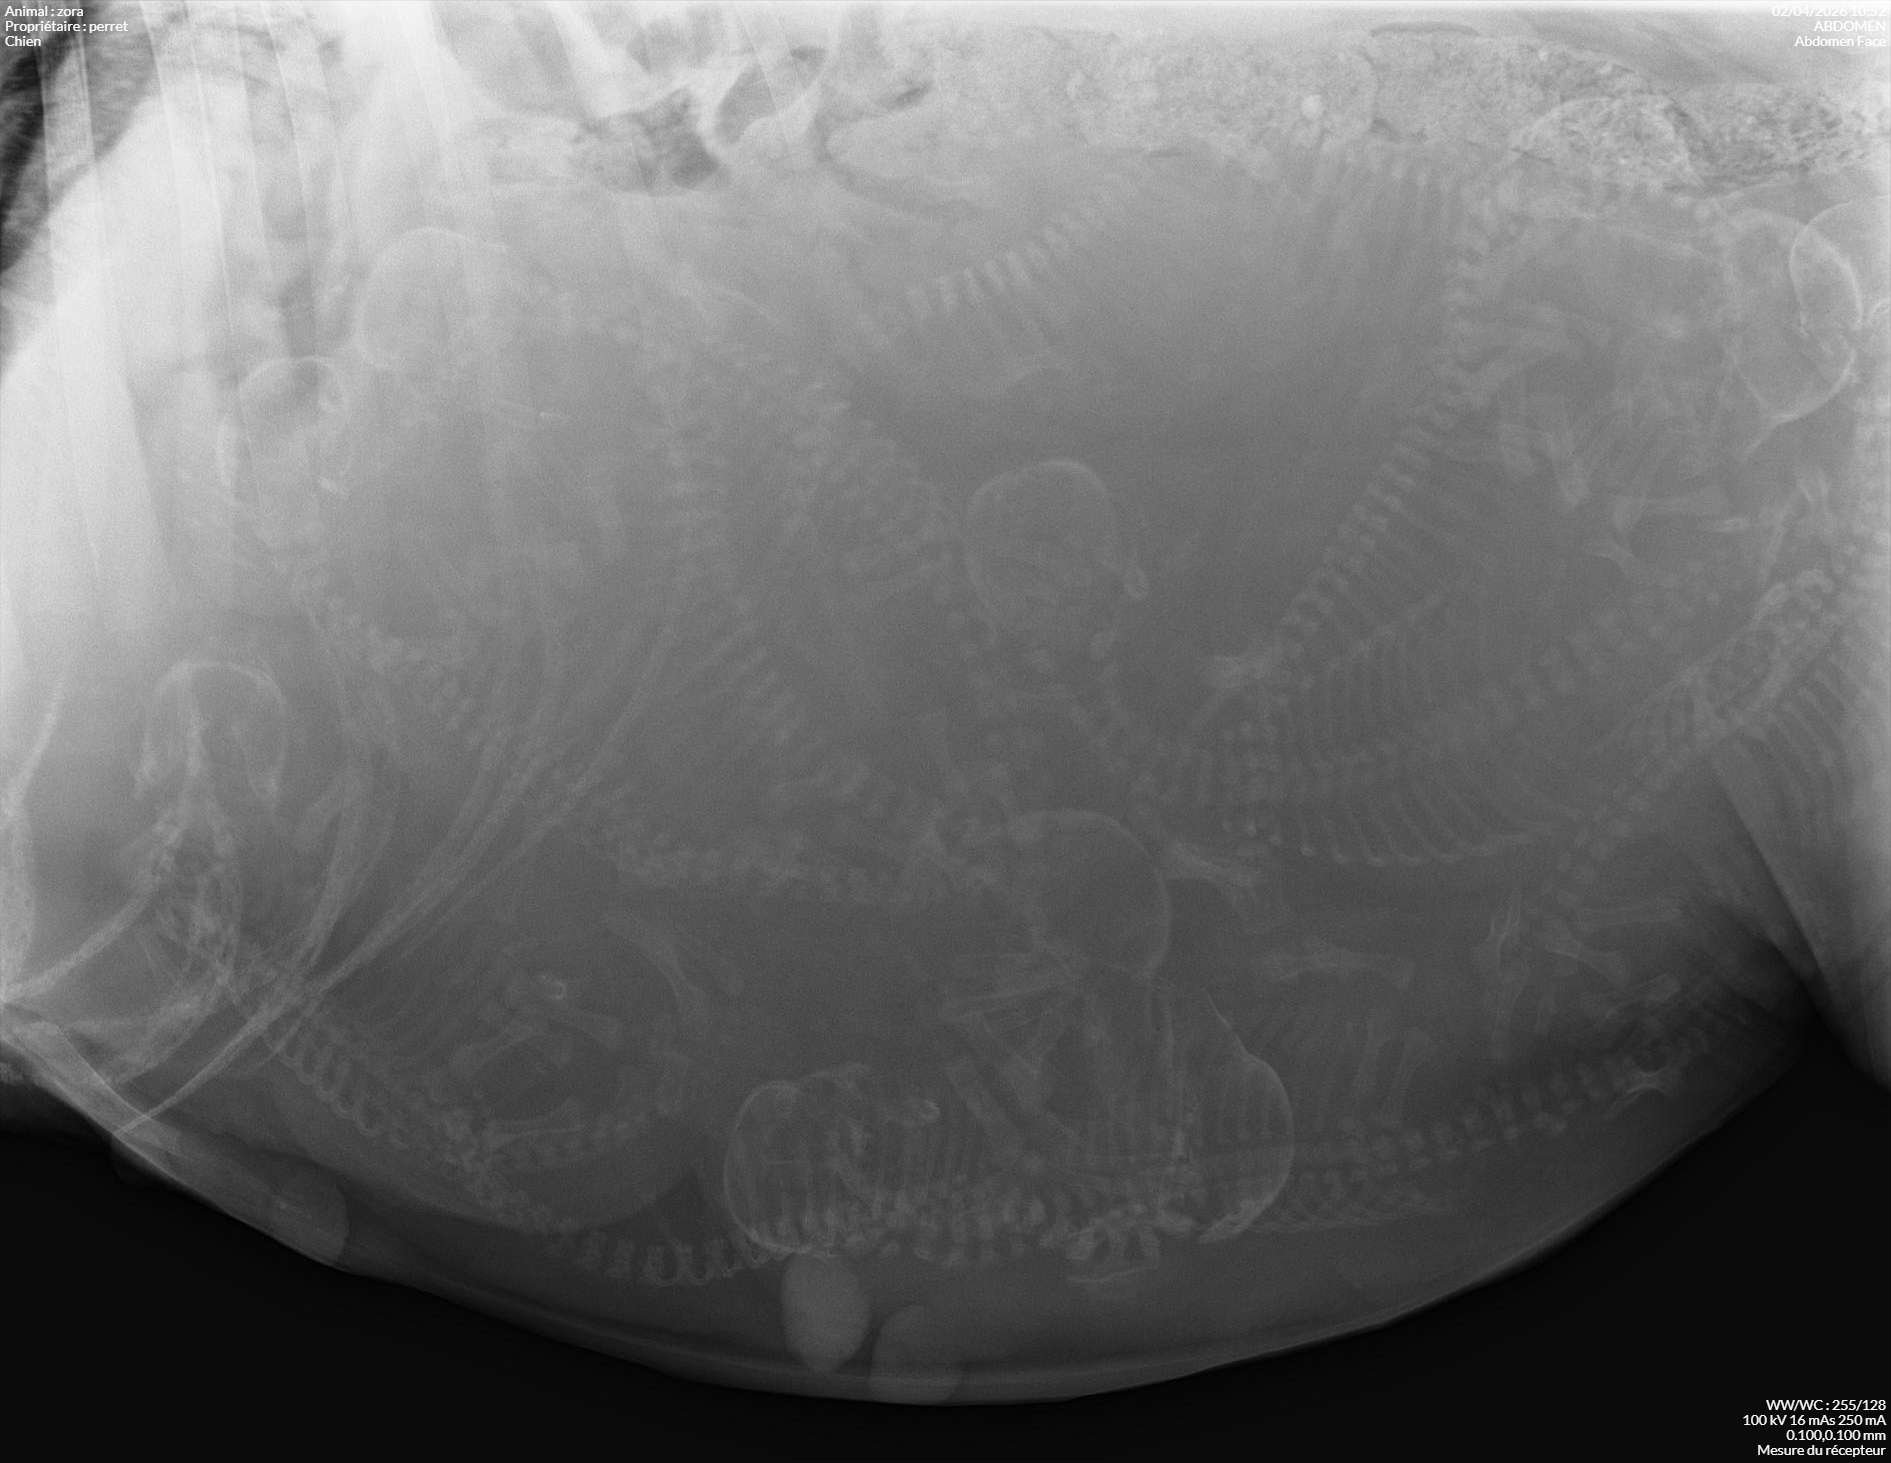

Zora et ses 11 bébés

Radio Zora 2_perret_zora_2.jpg